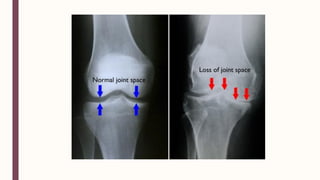

■ – – – – – ■ Martínez-Elizondo, P. Introduccióna la Reumatología. 5ta ed. México: Fondo editorial del Colegio Mexicano de Reumatología (2011)